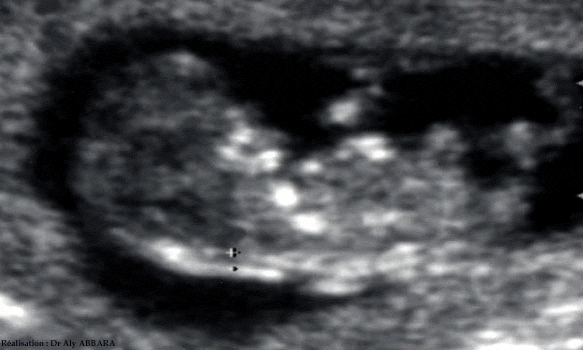

Fœtus à 11 et demi semaines d'aménorrhée

Mise en évidence de la clarté nucale